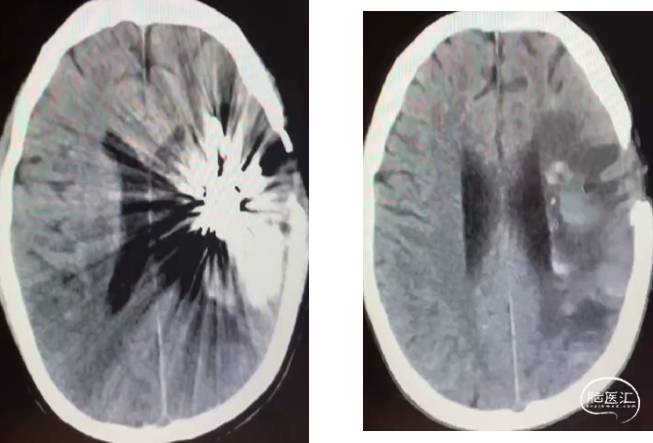

男,26岁,

因“反复四肢抽搐3年余,加重10天余”于入院。

2009年曾行左侧脑出血开颅手术,具体不详。

神志清醒,对答切题,右上肢肌力1级,右下肢肌力4级,其余肢体肌力肌张力大致正常。

术前MRI平扫+DWI

诊断:

1、左侧额颞叶脑动静脉畸形

2、继发性癫痫

3、左侧基底节区、额颞叶脑出血术后